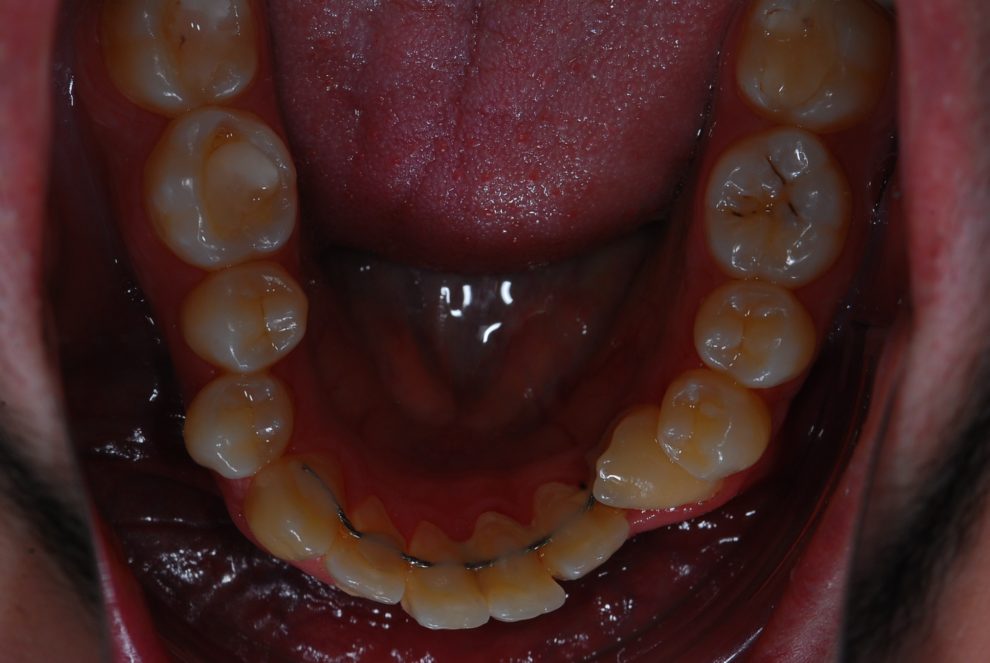

Ortodoncia + Mordida abierta

Nuestro paciente Manuel Vergara Gil acudió a nuestra clínica, y se le hizo una Ortodoncia.